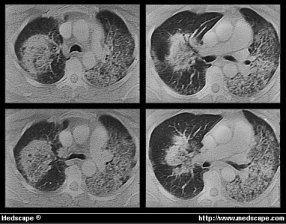

lesiones en mucosa oral (Fig 2), así como nódulos pulmonares

(TAC, fig 3)

Enfermedad de Wegener con hemorragia pulmonar. El TAC muestra lahemorragia pulmonar en un enfermo con GW y disnea.